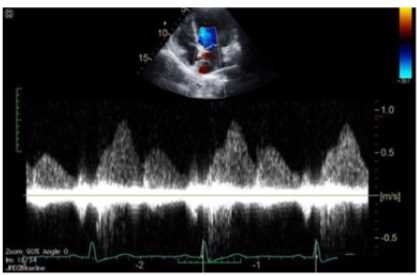

Which of the following does this Image represent?

1. Mitral valve inflow

2. Tricuspid valve inflow

3. Hepatic vein Doppler

4. Pulmonary vein Doppler

Answer(s): C

Explanation:

The image shows a pulsed-wave Doppler waveform with respiratory phasicity and distinct forward and reversed flow components characteristic of hepatic vein flow patterns. Hepatic vein Doppler typically displays a biphasic waveform with systolic (S) and diastolic (D) forward flow toward the heart and brief reversed flow during atrial contraction (A wave reversal), reflecting right atrial pressure changes.

Mitral and tricuspid inflow Doppler patterns show distinct E and A waves representing early and late diastolic ventricular filling but do not have the same flow reversal pattern. Pulmonary vein Doppler waveforms also differ, showing systolic and diastolic forward flows into the left atrium without the prominent reversed flow seen here.

The hepatic vein Doppler is commonly used in echocardiography to assess right atrial pressure and compliance, especially in conditions like constrictive pericarditis and right heart failure, where characteristic flow reversals and expiratory changes are observed.